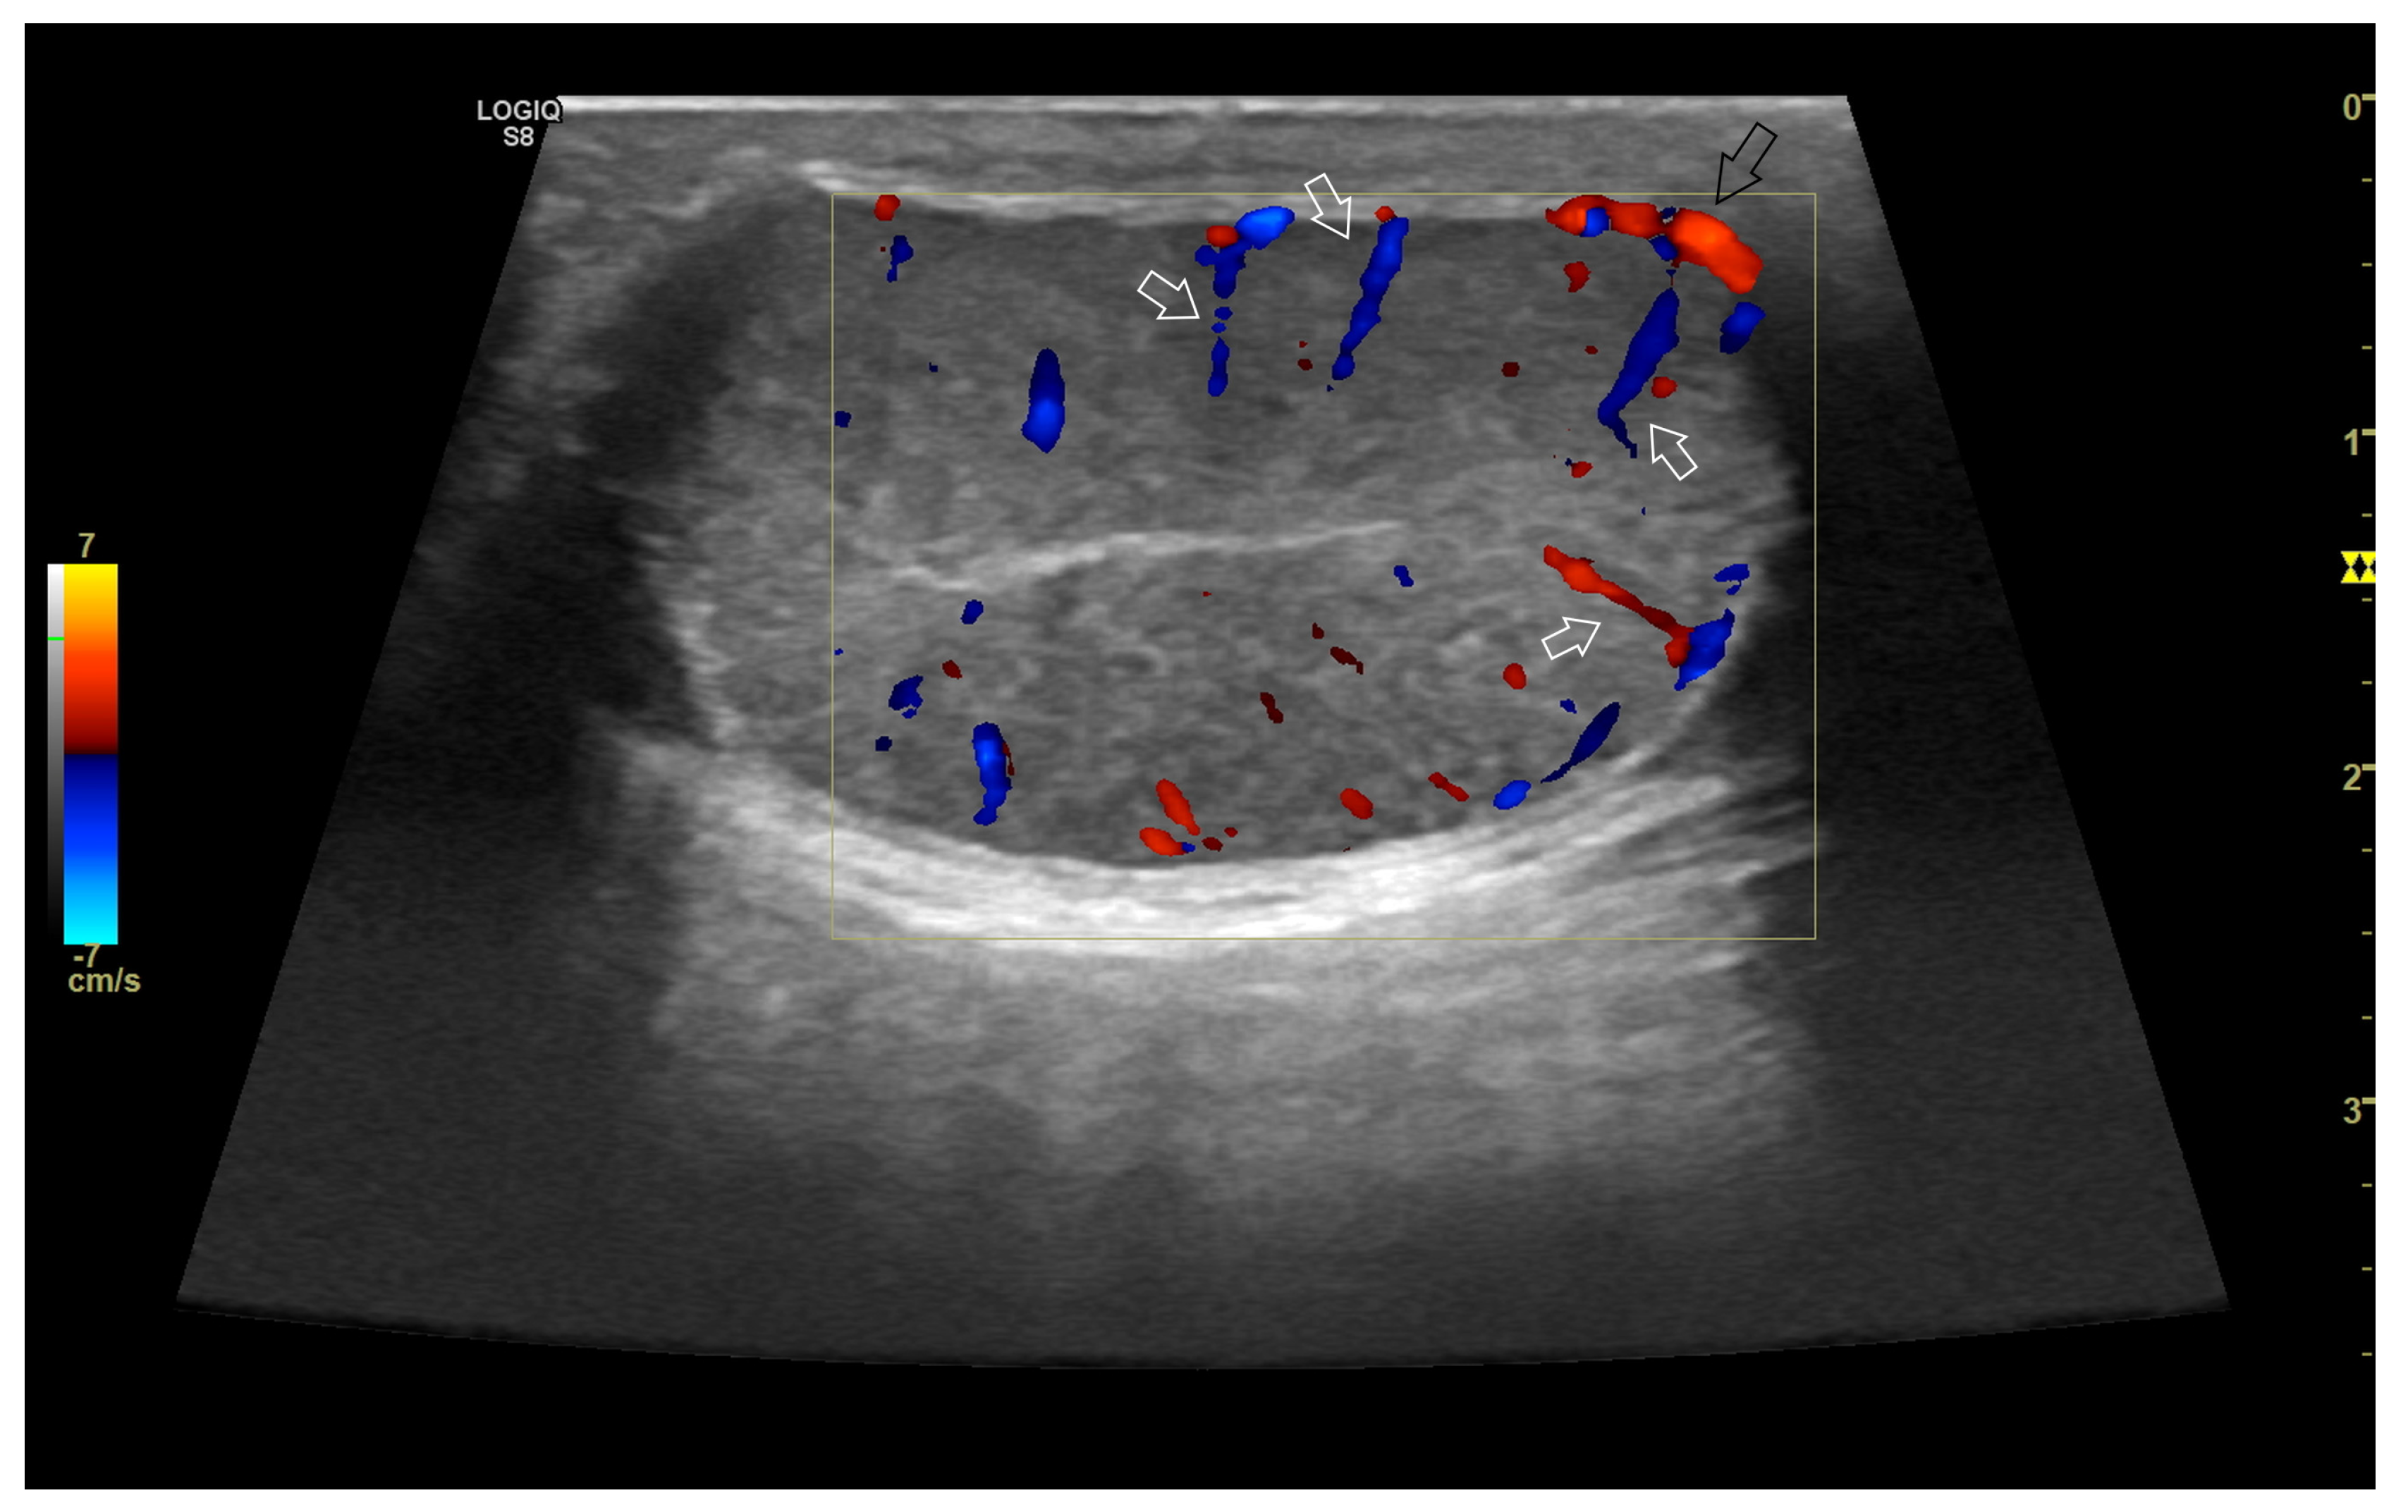

4. Colour Doppler and Power Doppler

4.1. Technology and Applications

4.2. Normal Findings

4.4. Abnormal Findings